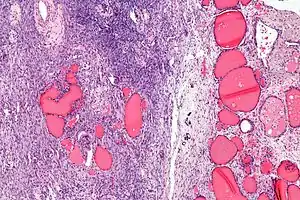

Micrograph of a struma ovarii. Characteristic thyroid follicles are seen on the right, and ovarian stroma on the left. H&E stain.

A struma ovarii (literally: goitre of the ovary) is a rare form of monodermal teratoma that contains mostly thyroid tissue, which may cause hyperthyroidism.[1]